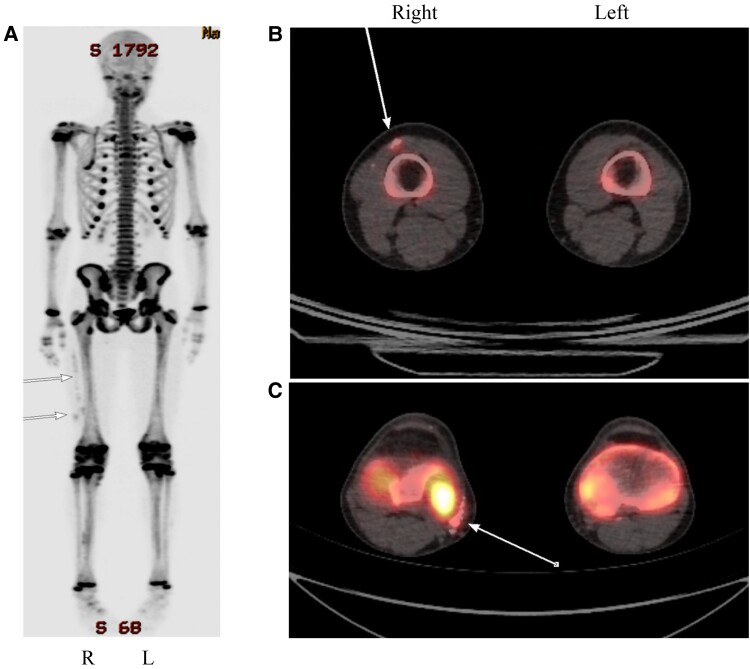

Progressive osseous heteroplasia (POH) is a rare autosomal-dominant hereditary bone disorder caused by inactivating pathogenic variants in GNAS1. POH is characterized by progressive cutaneous ossification and heterotopic ossification in skeletal muscles and subdermal connective tissues. Understanding of the natural history and phenotypic heterogeneity of the illness is incomplete. We report 2 affected male subjects with a milder than usual clinical course, highlight their clinical presentations and molecular correlates, and propose sodium 18F-fluorine positron emission tomography (PET) scanning as a sensitive technique for POH diagnosis and management.